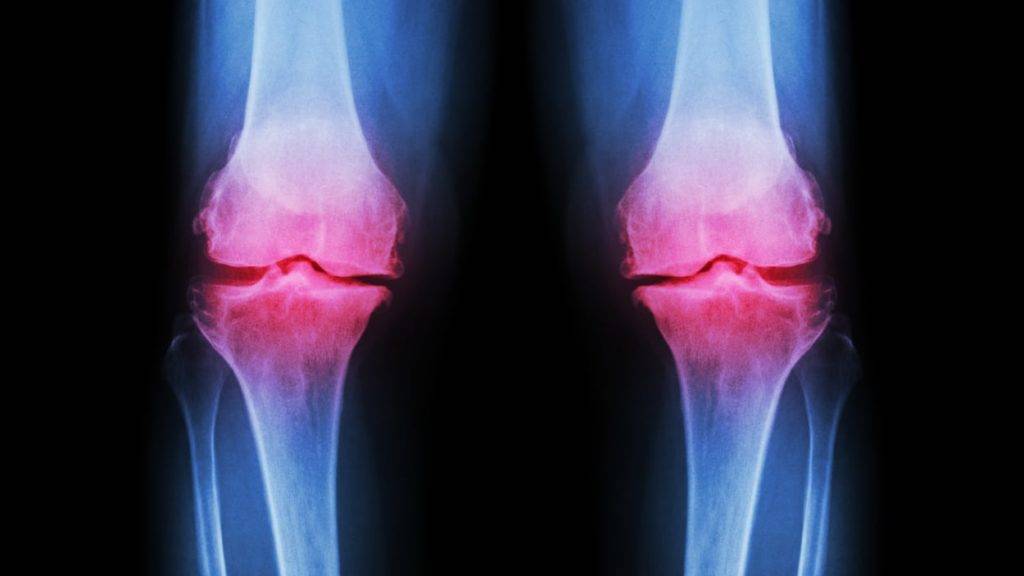

- Коленный сустав. Здесь часто развиваются неспецифические гнойные, а также гонорейные воспалительные процессы. Гнойные артриты могут протекать тяжело, колени болят очень сильно, больному часто требуется госпитализация, иногда даже оперативное вмешательство. Гонорейные артриты коленного сустава при своевременном лечении проходят без последствий, но при отсутствии лечения течение может переходить в хроническое с формированием анкилоза.